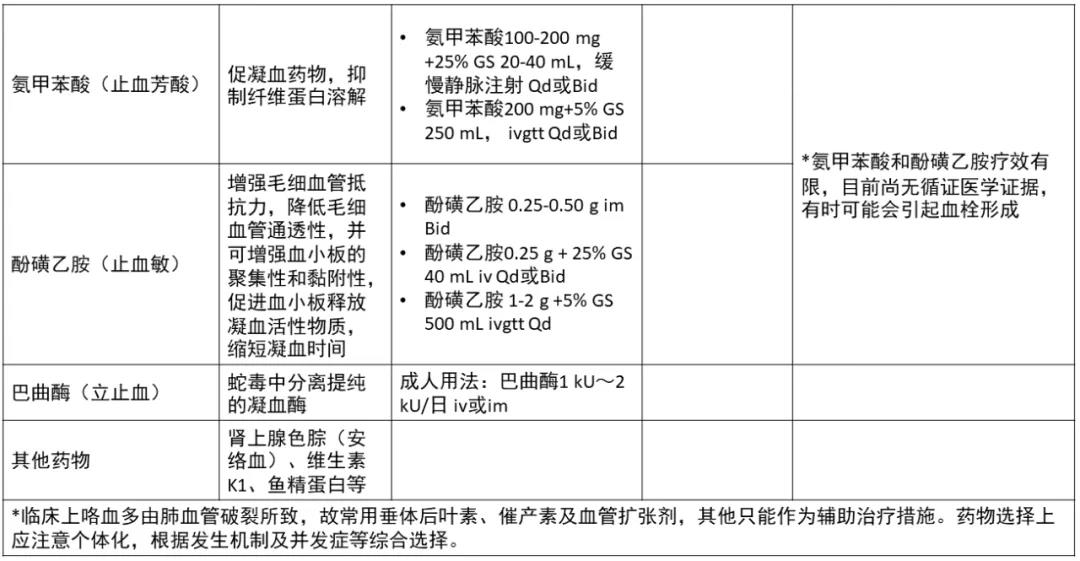

肺癌患者咯血咋处理?这有一份锦囊请收好!

肺癌患者咯血咋处理?这有一份锦囊请收好!

肺癌相关性咳嗽的治疗药物

肺癌相关性咳嗽的治疗药物